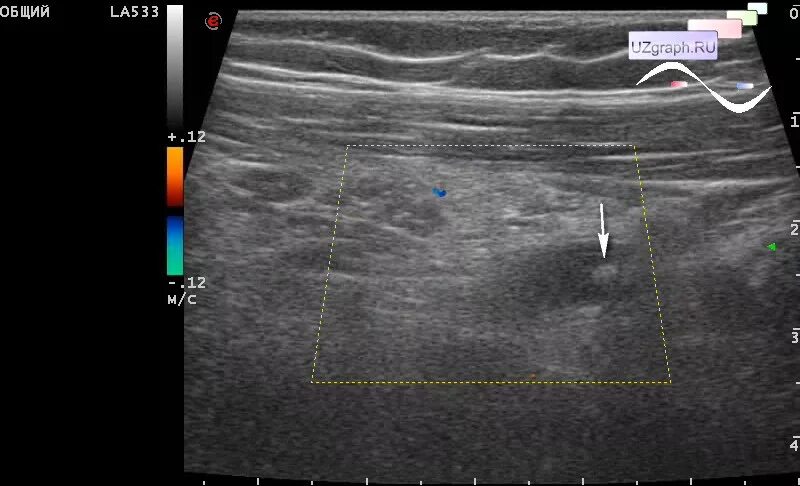

Аппендицит на узи можно ли